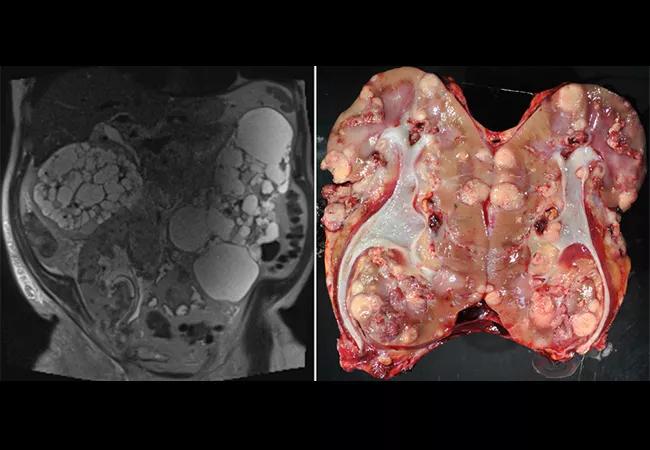

Featured image: Left: Coronal T2-weighted magnetic resonance imaging series demonstrating multiple fluid-filled cysts in the native kidneys with innumerable T2 dark hypoenhancing lesions throughout the kidney allograft. Right: Gross pathology of nephrectomy specimen, renal cell carcinoma, multifocal, clear cell subtype with focal rhabdoid areas, International Society of Urological Pathology grade 4 with invasion into renal vein, renal sinus and perinephric fat, and neoplasm extending to perinephric fat margin of excision.

Used with permission from Elsevier. This figure originally appeared in: Gross MD, Hassanein M, Myles JL, Augustine JJ, Wee A. Donor-Derived Renal Cell Carcinoma in a Kidney Allograft: A Case Report. Transplant Proc. 2022 Jan-Feb;54(1):123-125. doi: 10.1016/j.transproceed.2021.11.017. Epub 2022 Jan 1. PMID: 34980506.